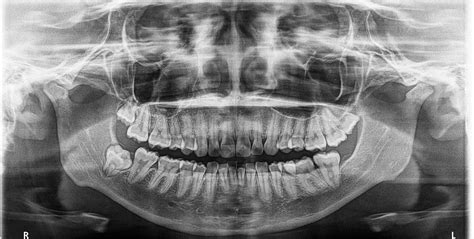

La macrodoncia es una condición dental poco común que se caracteriza por tener uno o varios dientes que son significativamente más grandes de lo normal. Esta anomalía puede afectar a cualquier diente en la boca, pero es más frecuente en los incisivos centrales superiores.

Dado que los dientes presentan diferentes tamaños, la sonrisa resultante no es armónica ni está equilibrada. Es importante conocer otro tipo de situaciones que, a priori, pueden confundirse con la microdoncia y la macrodoncia. Así, es relativamente frecuente pensar que un niño padece de macrodoncia cuando, en realidad, se encuentra en la fase de la dentición mixta. Los dientes temporales tienen un tamaño menor en comparación con los definitivos, por lo que a simple vista se apreciará una diferencia de tamaño.